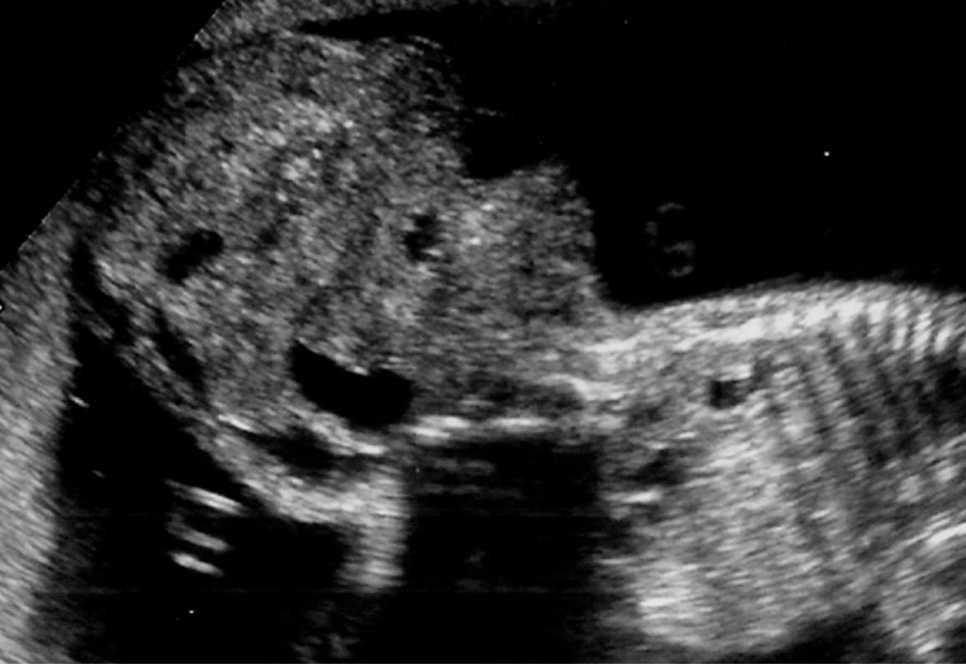

Gestante de 34 años de edad, sin antecedentes patológicos de interés, con antecedentes obstétricos de un aborto espontáneo y una cesárea anterior, realizada en el año 2003, en que dio a luz un recién nacido que falleció por depresión neonatal y síndrome de distrés respiratorio. Fue remitida en su tercera gestación a la unidad de Diagnóstico Prenatal del Hospital Universitario Materno Infantil de Canarias en la semana 21. El feto estaba en presentación cefálica, con movimientos activos espontáneos y una biometría acorde con la edad gestacional. La placenta era normoinserta y la cantidad de líquido amniótico era normal. Destacaba la presencia de una tumoración lumbosacra de 38 × 38 × 42 mm de diámetro, de contorno bien definido, contenido mixto con predominio sólido, localización lumbosacra, con componente intrapélvico que ocupaba la fosa ilíaca derecha fetal. No afectaba a la región genital, y los genitales externos masculinos eran normales. No había relación con el sistema urogenital ni con la columna (figs. 1 y 2). El estudio con Doppler color reveló una densidad vascular moderada y dependiente de los vasos paravertebrales, sin flujos turbulentos. El resto del estudio morfológico transcurrió dentro de la normalidad, sin evidencias de alteraciones en otras estructuras. Asimismo, se completó el estudio descartando la presencia de signos de sobrecarga cardíaca o de anemia fetal (índice de pulsatilidad de ductus venoso dentro de la normalidad, con un valor de 0,56; velocidad máxima de flujo en arteria cerebral media de 24 cm/s, no sugestivo de anemia fetal). Se concluyó la exploración con la orientación diagnóstica de teratoma sacrococcígeo tipo II, de componente mixto, moderadamente vascularizado, sin signos de insuficiencia cardíaca.

Figuras 1 y 2. Ecografía realizada en la semana 21, donde se aprecia una tumoración lumbosacra de 38 × 38 × 42 mm, de contenido mixto, contorno bien definido, con componente intrapélvico, que ocupa la fosa ilíaca derecha fetal.